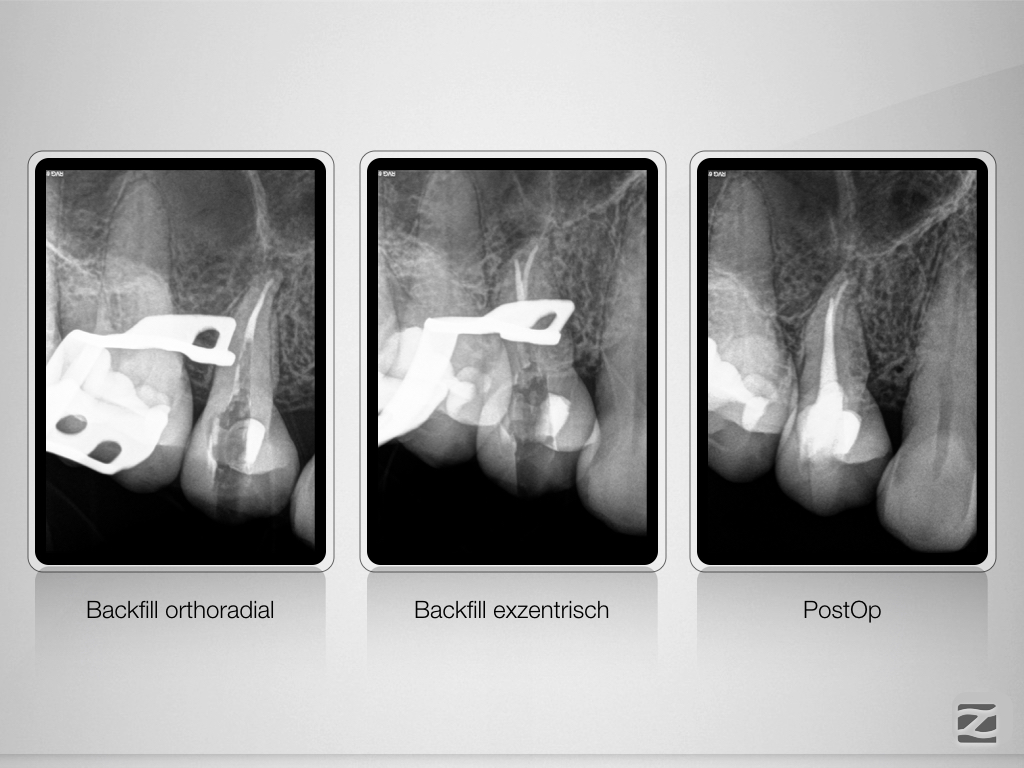

15D.010

Was wäre, wenn …?